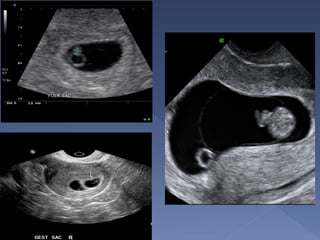

 Earliest sign of

pregnancy

 seen at 4-4.5 weeks

 It is intradecidual

 Surrounded by

decidual reaction

 Can be used for

dating.

 A normal gestational

sac grows by 1 mm

per day.

 its normal eccentric location: it is

embedded in endometrium, rather than

centrally within the uterine cavity

 presence of a yolk sac : seen at

approximately 5.5 weeks or with a beta-

HCG of ~7000m IU/ml

 presence of the double decidual sign

 Seen at 5 weeks

gestation

 Differentiates

true from pseudo

gestational sac

 Seen at 20 mm

sac diameter

abdominally and

8 mm sac

diameter

vaginally

 Seen at 6

weeks vaginally

 Should be seen

at sac diameter

of 18mm

vaginally and

25mm

abdominally

 Heart beat is

seen at CRL of

5mm vaginally

 Gestational sac – 4 to 5 weeks

 Yolk sac – 5 to 6 weeks

 Fetal pole - 6 to 7 weeks

 Cardiac Activity - 6 to 7 weeks.